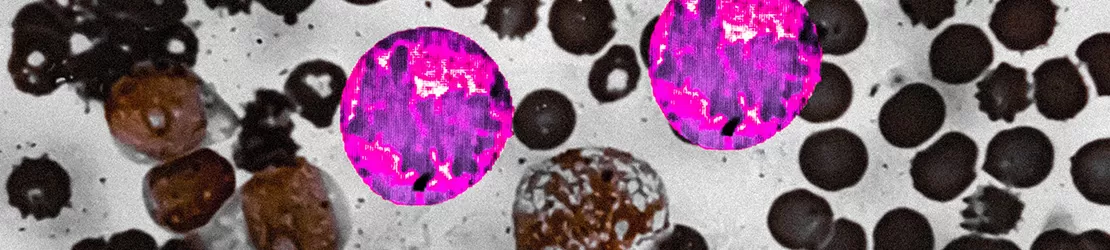

Sindromul mieloproliferativ denumește grupul de boli hematologice cronice caracterizate prin producerea excesivă de celule sanguine (globule roșii, globule albe și/sau trombocite) de către măduva osoasă. Aceste afecțiuni apar ca urmare a unei mutații genetice la nivelul celulelor stem hematopoietice, care determină înmulțirea necontrolată a acestor celule.

Studiu de maduva osoasa (BMD) aratand trombocitopenie amegacariocitara la microscop